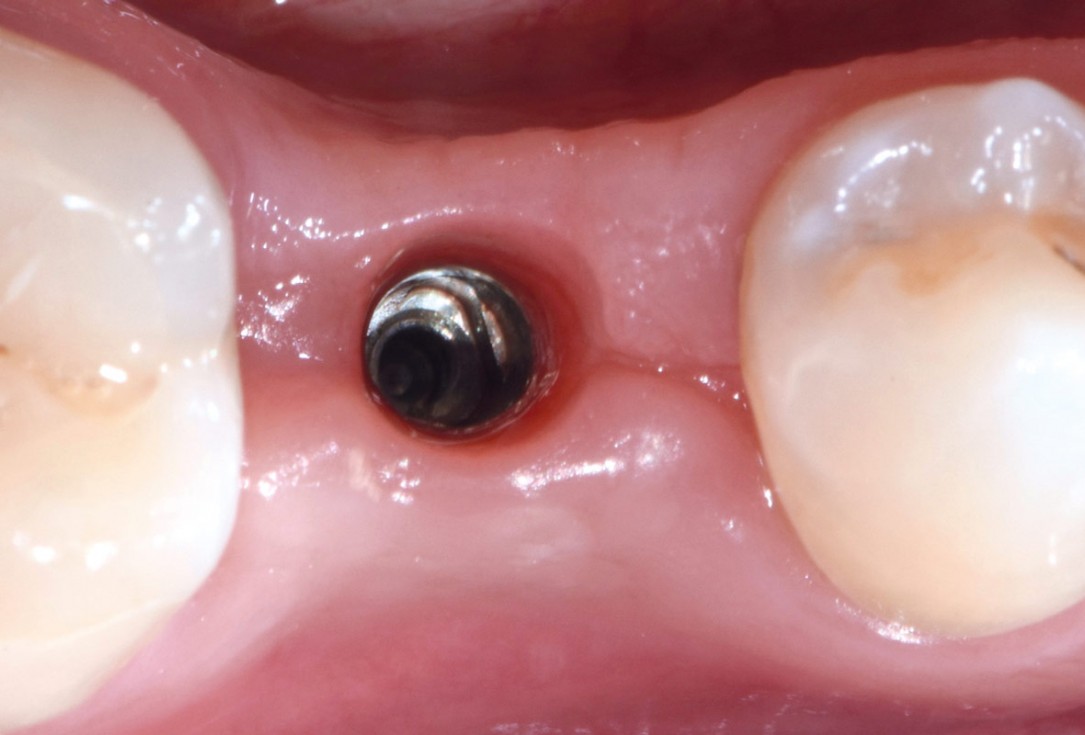

10/17 - Healing at 2 months: insufficient buccal volumeApplication of mucoderm® for soft tissue management around single implants at second stage surgery Dr. C. De Annuntiis

11/17 - Implant surrounded by bone: it´s possible to augment just soft tissueApplication of mucoderm® for soft tissue management around single implants at second stage surgery Dr. C. De Annuntiis